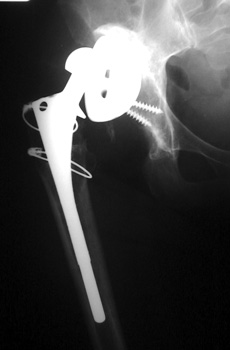

No prior studies available. Abnormally widened interfaces about femoral component at Gruen zones 1, 6, and 7. Osteolysis at Gruen zone 5 with marked thinning of femoral cortex placing patient at risk for pathologic fracture.

Cement fracture Gruen zone 6 close up next slide